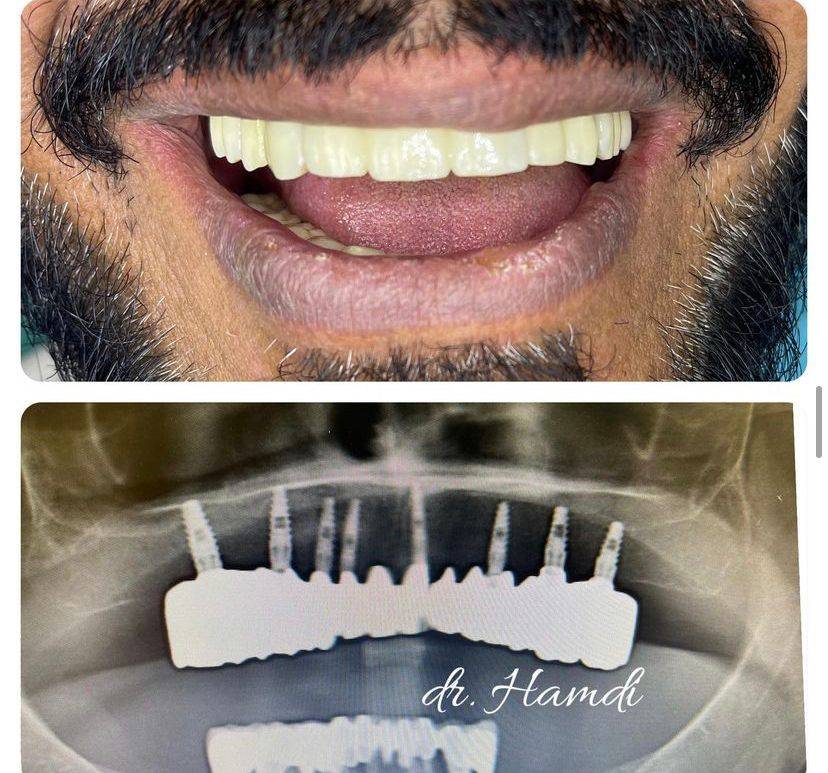

الدكتور حمدي العوضي

تخرج الدكتور حمدي العوضي من كلية طب الأسنان في عام 2003 ، وأنهى فترة تدريبه ، وعمل على الفور في مستشفى اليمامة (وزارة الصحة) حيث عمل كممارس أسنان عام لمدة 4 سنوات.

أجرى الدكتور حمدي العوضي أكثر من 50.000 عملية زراعة أسنان وترقيع عظمي خلال السنوات العشر الأخيرة من ممارسته.